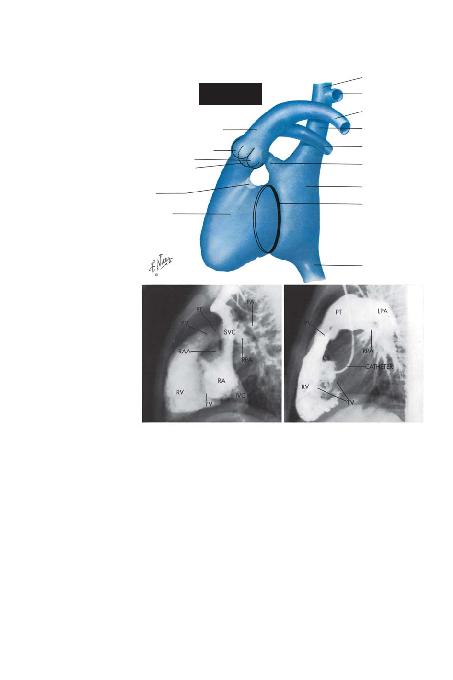

Sa¤ Kalp, Frontal Projeksiyon (Sayfa 26). Kalbin sa¤ ta-

raf> genelde, venöz angiyokardiyografi ve seçici enjeksiyon ile

iyi bir flekilde görüntülenebilir. Frontal (anteroposterior) pro-

jeksiyonda superior ve inferior vena kava omurgan>n sa¤>nda

düz bir çizgi halinde, sa¤ atriyuma karfl>t yönden giren yap>lar

olarak tespit edilirler. Sa¤ atriyumun serbest duvar> incedir ve

kontrastla dolu atriyumun sa¤ s>n>r> ve kardiyak silüetin sa¤ s>-

n>r> aras>ndaki bofllukla temsil edilir. Normalde bu boflluk 2 ila

3mm aras>ndaki bir çapa sahiptir. Bu bofllu¤un geniflli¤indeki

bir art>fl sa¤ atriyum duvar>n> perikardiyumdan ay>ran perikar-

diyal efüzyon s>v>s>n>n bir göstergesidir.

Sa¤ atriyal apendiks, sa¤ atriyumun üst k>sm>ndan me-

diale ve yukar> do¤ru uzan>r. Trikuspid kapak frontal projek-

siyon temel al>nd>¤>nda, oblik bir düzlemde durmaktad>r ve

kusplar>n yap>flma çizgileri s>kl>kla omurgan>n üzerindeki bir

elips fleklinde saptan>r. Trikuspid annulusun inferior s>n>r>,

inferior vena kavan>n sa¤ atriyuma girifline komfludur. Koro-

ner sinüsün aç>l>m yeri de ayn> bölgededir. Bu bilgiler, sa¤

ventrikül kateterizasyonu yap>l>rken ak>lda tutulmal>d>r çün-

kü koroner vene giren ve büyük kardiyak vene do¤ru ilerle-

yen bir kateter, trikuspid kapaktan geçen ve sa¤ ventrikülün

d>fl ak>m yola¤>nda bulunan bir kateter ile, frontal projeksi-

BÖLÜM I -- LEVHA 26

SA/ KALBMONER TRUNK; PV: PULMONER KAPAK; RAA: SA/ ATRUZANTI; RV: SOL VENTRATRKAVA; LPA VE RPA: SOL VE SA/ PULMONER ARTERLER

LATERAL ANGKATETER, VENTRGÖSTERMEKTED

SA/ KALBBOfiLUKLARININ

LATERAL PROJEKS